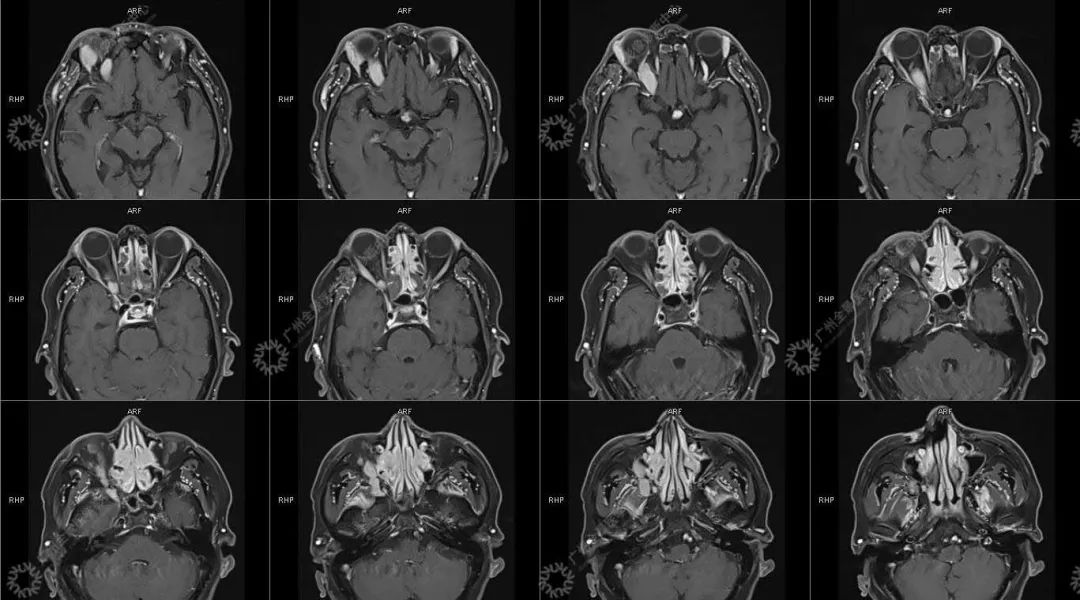

患者:男性, 71 岁

主诉:视力下降 2 年

现病史:双眼部隐痛、流泪,视力下降 2 年

结合影像及实验室检查,临床最终考虑 IgG4 相关性疾病。